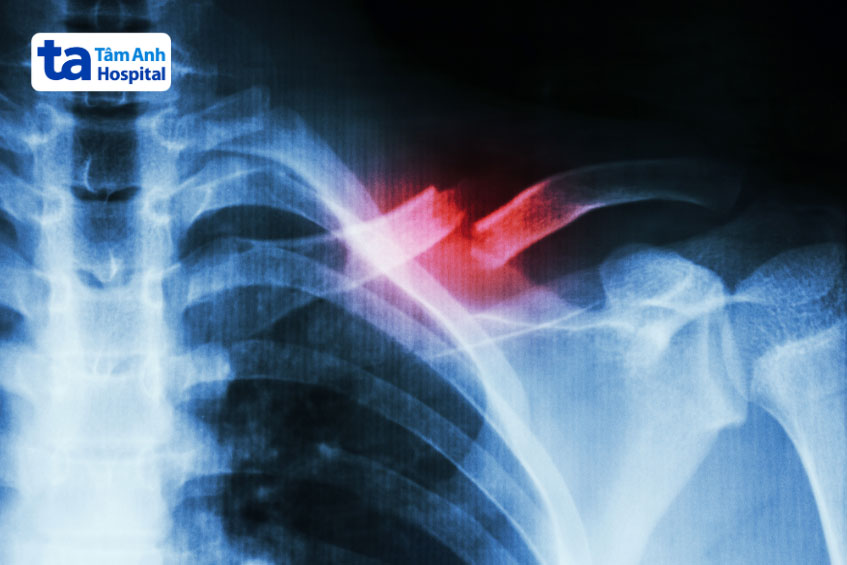

Gãy xương cũng là một trong những nguyên nhân gây đau vùng cổ vai gáy bên trái, nhất là những xương ở gần khu vực này như:

Xương đòn (còn gọi là xương quai xanh) là xương dài nối xương ức và hệ thống đai vai – cánh tay. Xương này được xem như một thanh chắn, cho phép vai hoạt động tối ưu, đồng thời bảo vệ các cấu trúc quan trọng như phổi, đám rối cánh tay, bó mạch dưới đòn…

Ngã chống tay khiến phần vai va chạm mạnh có thể trực tiếp hoặc gián tiếp gây gãy xương đòn. Ngoài ra, tai nạn giao thông, lao động hoặc chấn thương thể thao cũng có khả năng làm gãy xương quai xanh. Lúc này, vùng vai có thể đau, sưng, bầm tím và hõm xuống khiến người bệnh gặp khó khăn khi cử động vai.